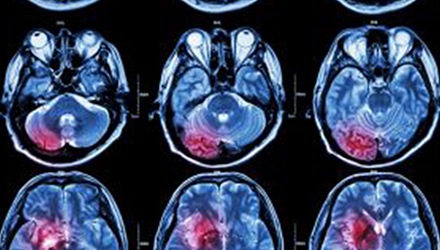

在這項研究中,研究人員使用功能核磁共振成像(fMRI)觀察大腦中血液含氧量的變化。研究人員首先研究了耳鳴患者和無耳鳴者的大腦活動,其目的是比較兩組受試者大腦處理情緒的方式。

在功能磁共振成像檢查中,受試者分別聽30種“愉悅”的聲音、30種“不愉快”的聲音和30種“中性”的聲音。這些聲音包括小孩咯咯笑,嬰兒啼哭,以及熱水壺?zé)_的聲音。

功能磁共振成像的結(jié)果顯示,當(dāng)暴露于情緒性聲音下,耳鳴患者大腦不同區(qū)域的活動比沒有耳鳴者的活動更強(qiáng)烈。接著,研究人員進(jìn)行了更深入的研究:耳鳴患者的大腦活躍性和耳鳴嚴(yán)重程度的關(guān)系。